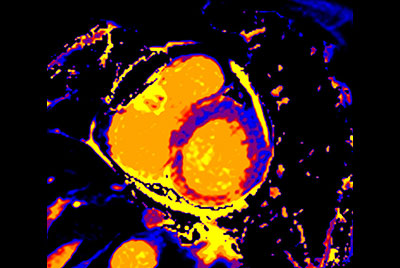

Myocardial infarction with T1/T2 Mapping